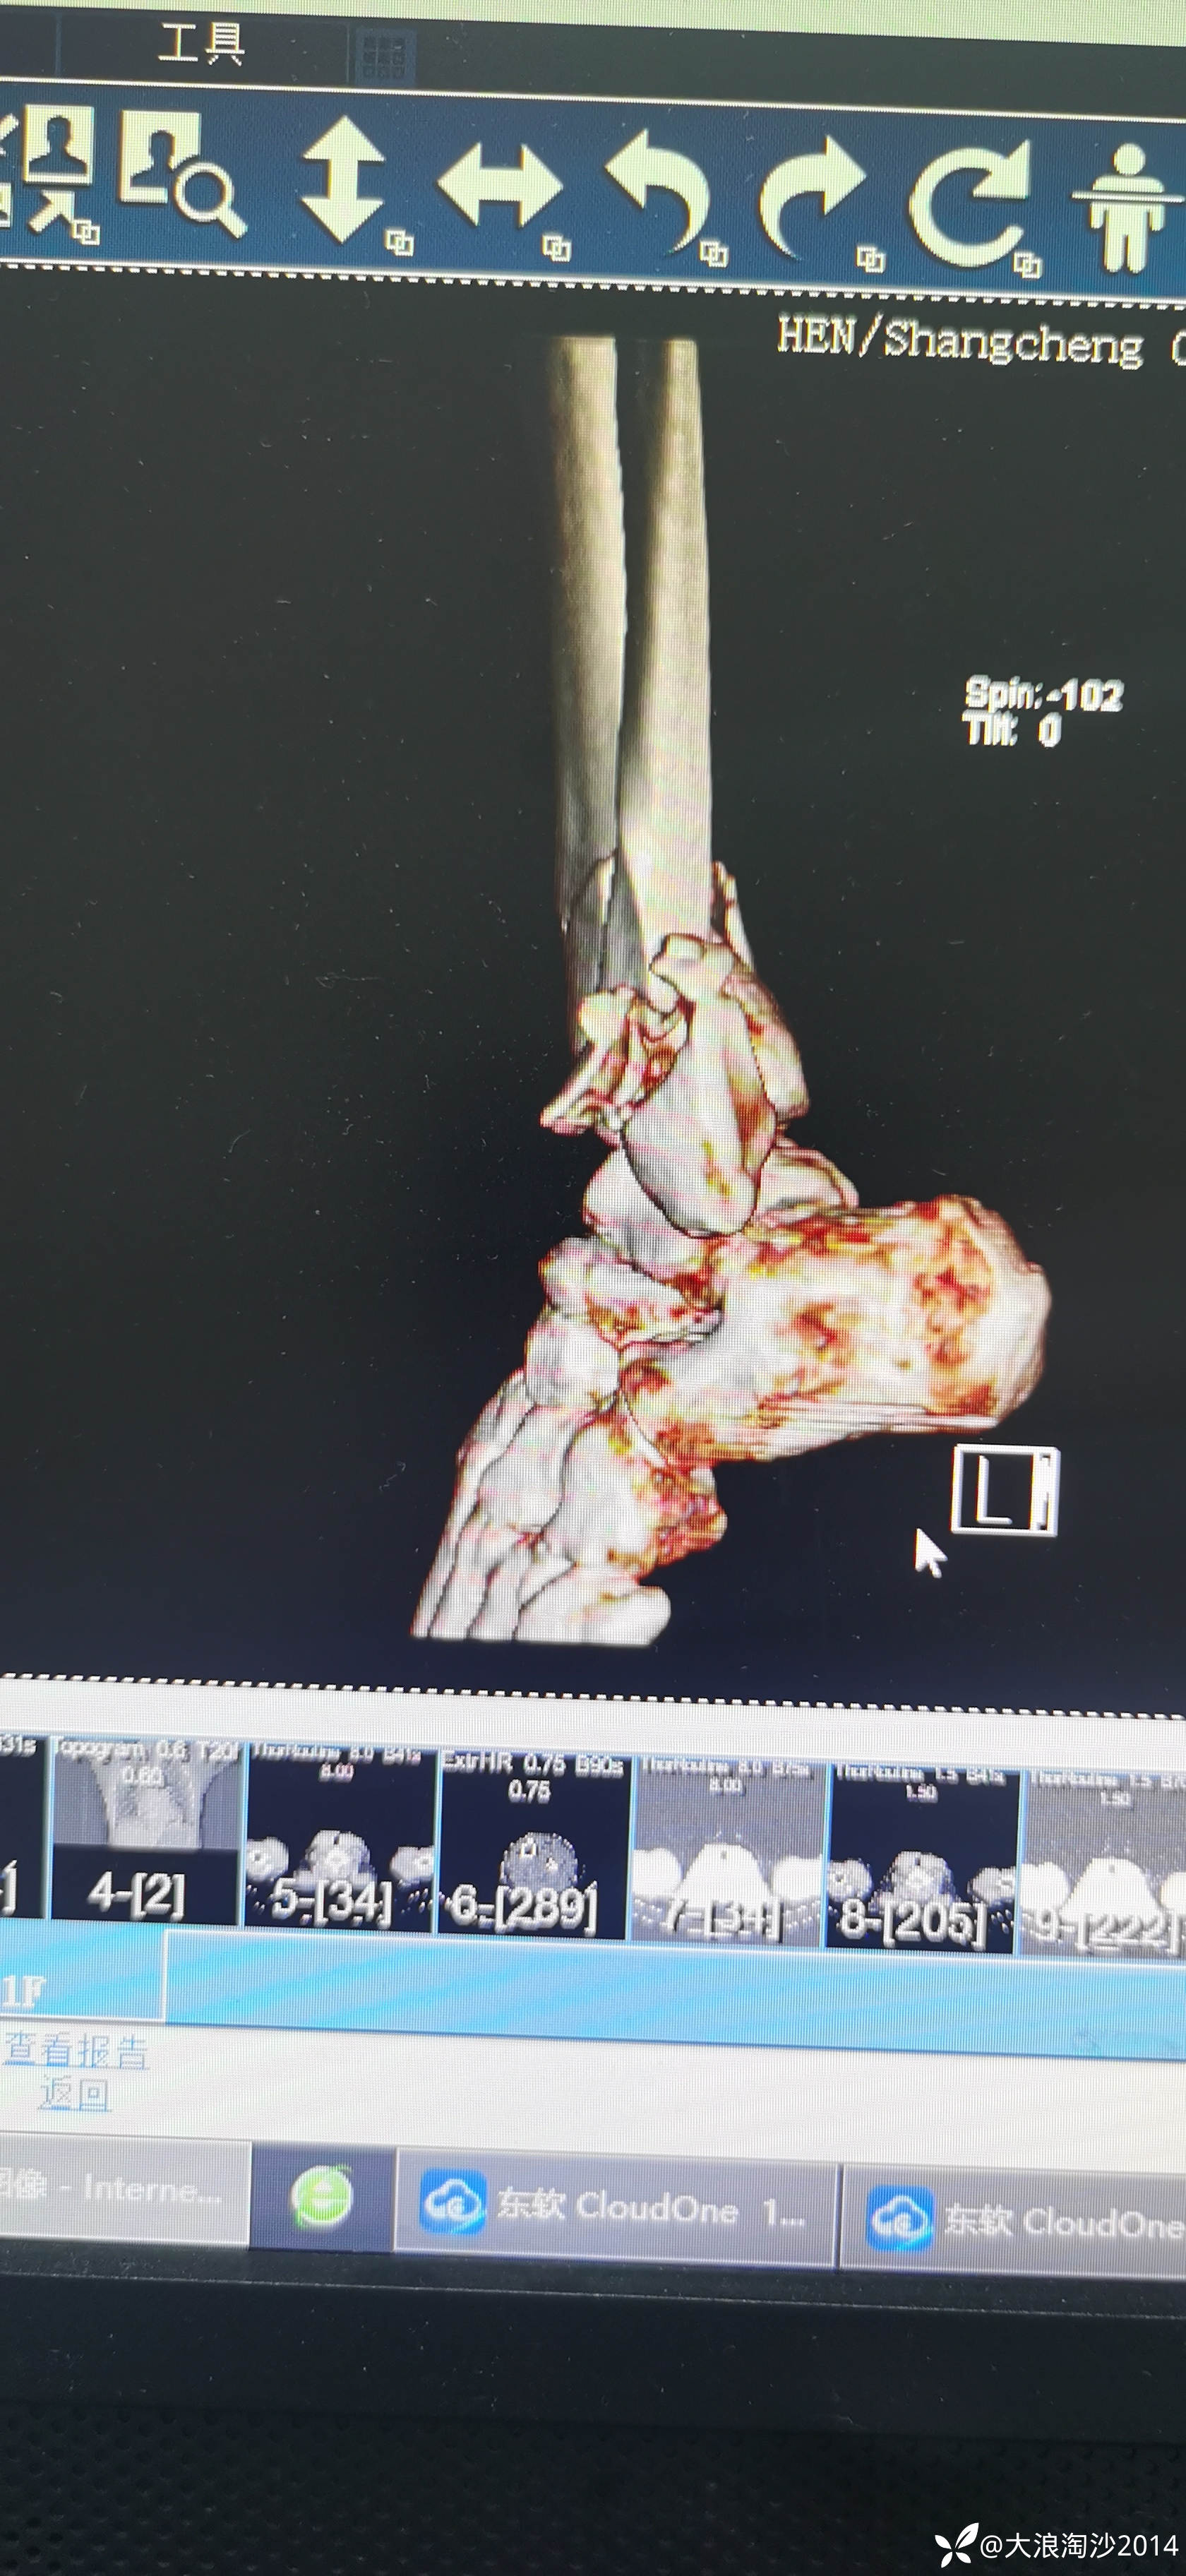

一65岁女性患者,偏瘦,体重75斤,车祸外伤致左胫腓骨远端骨折,入院后消肿后,病人可以用皮包骨头形容,考虑胫骨远折端不适合用内侧插板(mippo技术),病人太瘦,如取两个切口分别处理胫腓骨,切口容易出现问题,因此采用前外侧一个切口处理胫腓骨远端骨折(片子顺序上传有点乱)